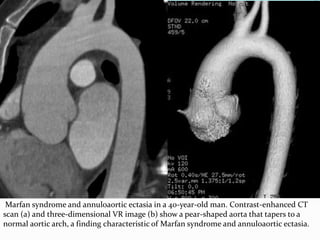

ANNULOAORTIC ECTASIA

 a condition characterized by dilated sinuses of Valsalva

most commonly associated with Marfan syndrome

 Other causes include homocystinuria, Ehlers-Danlos

 the appearance of the aorta in patients with Marfan

Marfan syndrome and annuloaortic ectasia in a 40-year-old man. Contrast-enhanced CT

scan (a) and three-dimensional VR image (b) show a pear-shaped aorta that tapers to a

normal aortic arch, a finding characteristic of Marfan syndrome and annuloaortic ectasia.